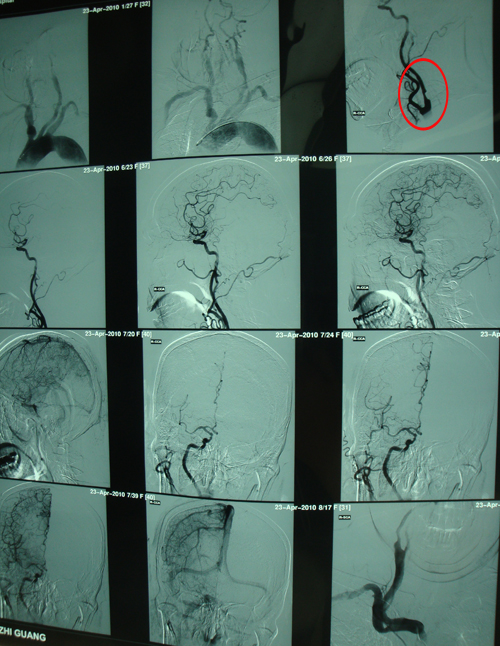

脑血管造影:双侧颈内动脉、眼动脉、右侧髂外动脉多发动脉粥样硬化性改变。

左侧颈内动脉血流通畅(黄色标记)

右侧颈内动脉中重度狭窄(红色标记)